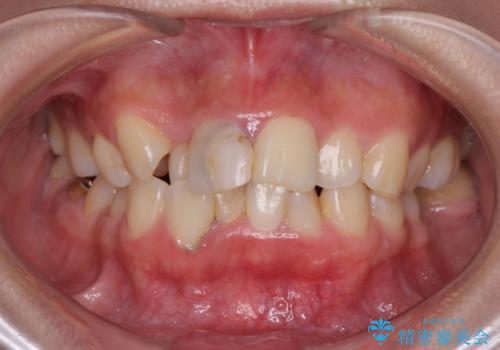

前歯のがたつき 深い噛み合わせを改善したい